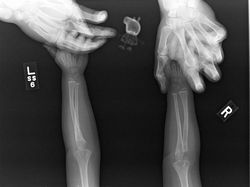

Coba perhatikan bagian telunjuk kakinya. (Foto: Brightside)

Ini adalah hasil X-ray pertama di dunia, diambil oleh Wilhelm RΓΆntgen pada 22 Desember 1895. (Foto: Brightside)